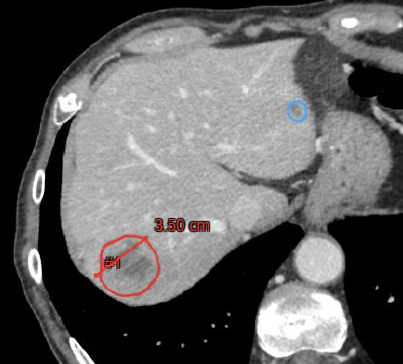

Ce travail s’intéresse à une problématique très concrète de la pratique quotidienne en imagerie oncologique : la mesure des lésions tumorales. En pratique clinique, l’évaluation de la réponse aux traitements repose largement sur les critères RECIST, qui utilisent le diamètre maximal des lésions cibles pour apprécier l’évolution de la maladie. Ces mesures, pourtant centrales dans la prise en charge des patients, restent aujourd’hui réalisées manuellement par les radiologues. Or, plusieurs études ont montré qu’elles peuvent présenter une variabilité entre lecteurs, notamment selon l’expérience du radiologue ou la morphologie des lésions.

Dans ce contexte, l’objectif de notre étude était d’évaluer un outil d’intelligence artificielle capable de segmenter automatiquement les métastases hépatiques au scanner et d’en extraire différentes mesures, notamment les diamètres compatibles avec les critères RECIST. Nous avons comparé ces mesures à celles réalisées par des radiologues ayant différents niveaux d’expertise afin d’en analyser la concordance et la variabilité.

Les résultats montrent que les diamètres mesurés automatiquement par l’IA sont très proches de ceux obtenus par les radiologues et, surtout, qu’ils se situent dans l’intervalle de variabilité habituellement observé entre lecteurs. Autrement dit, l’intelligence artificielle ne semble pas introduire de variabilité supplémentaire, mais reproduit plutôt les dynamiques de mesure observées entre radiologues. Ces résultats suggèrent que ces outils pourraient contribuer à standardiser les mesures utilisées pour le suivi des patients en oncologie tout en simplifiant certaines étapes du workflow.